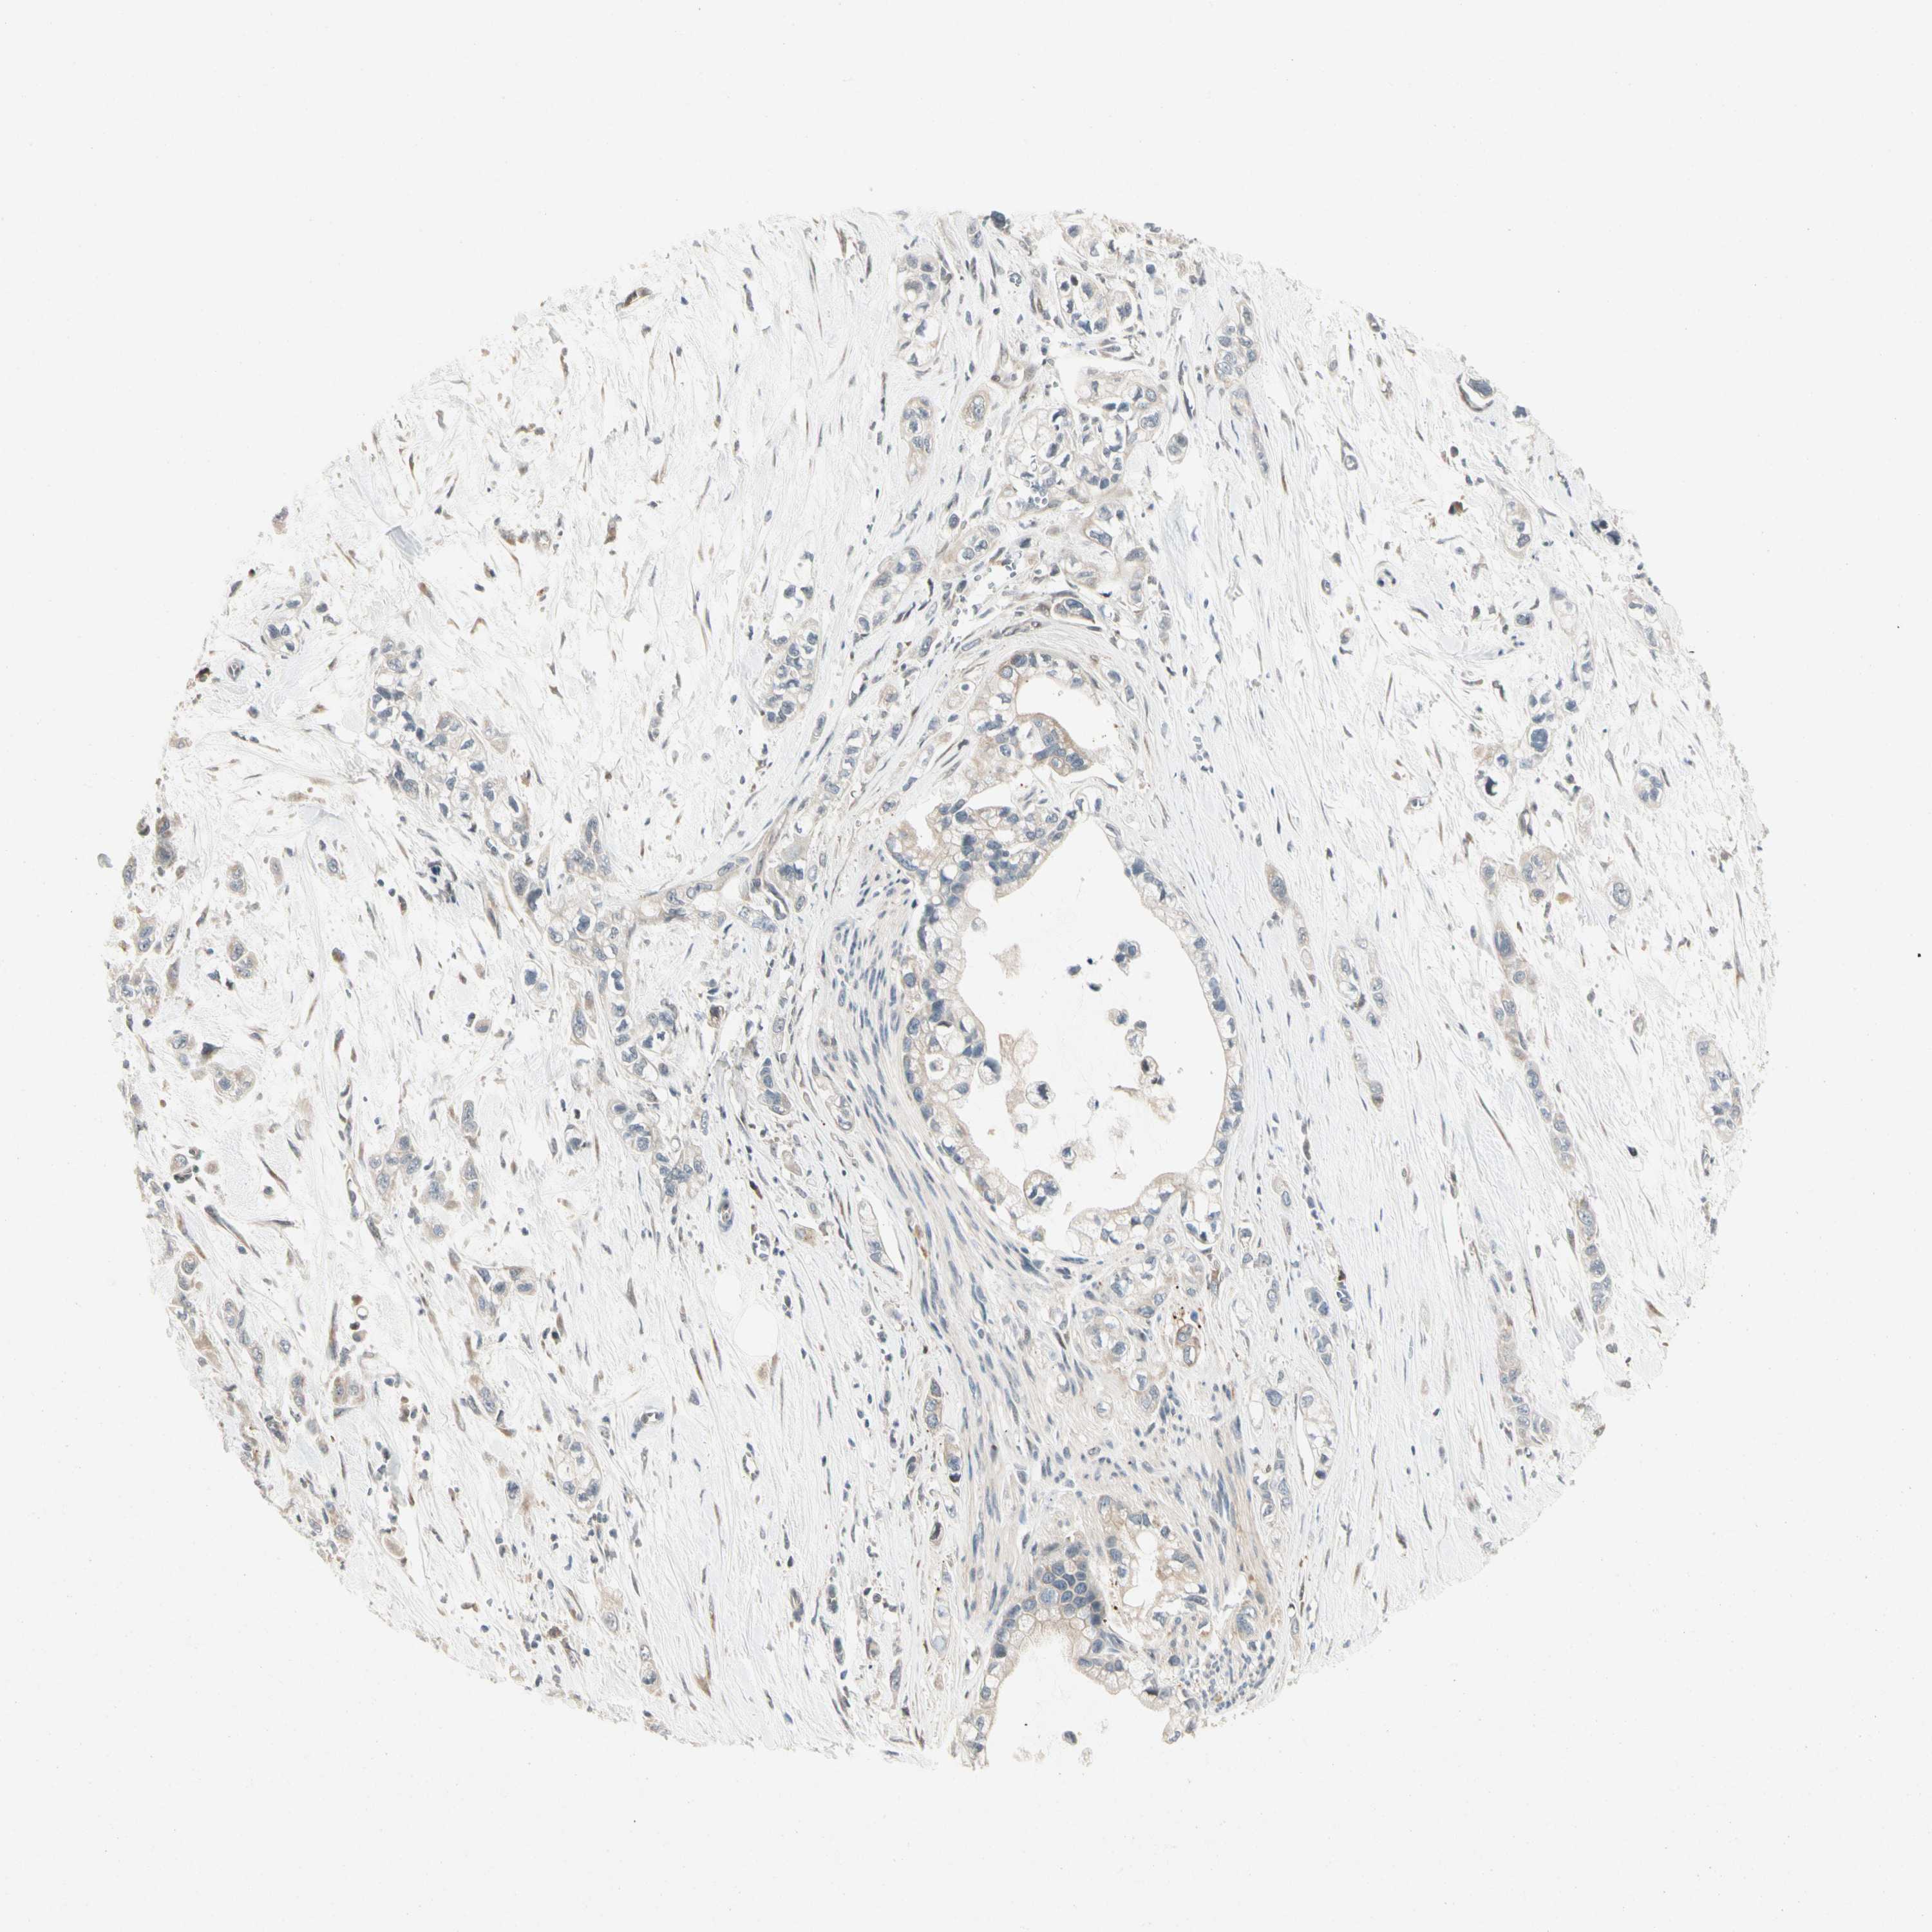

PANCREATIC CANCER - Protein expressioni

A mouse-over function shows sample information and annotation data. Click on an image to view it in a full screen mode. Samples can be filtered based on level of antibody staining by selecting one or several of the following categories: high, medium, low and not detected. The assay and annotation is described here.

Note that samples used for immunohistochemistry by the Human Protein Atlas do not correspond to samples in the TCGA dataset.

Antibody stainingi

Antibody staining in the annotated cell types in the current human tissue is reported as not detected, low, medium, or high, based on conventional immunohistochemistry profiling in selected tissues. This score is based on the combination of the staining intensity and fraction of stained cells.

Each image is clickable and will lead to virtual microscopy that enables deeper exploration of all samples and also displays staining intensity scores, fraction scores and subcellular localization as well as patient and tissue information for each sample.

Antibody HPA007859

Staining

High

Medium

Low

Not detected

Intensity

Strong

Moderate

Weak

Negative

Quantity

>75%

75%-25%

<25%

None

Location

Nuclear

Cytoplasmic/membranous

Cytoplasmic/membranous,nuclear

Adenocarcinoma, NOS